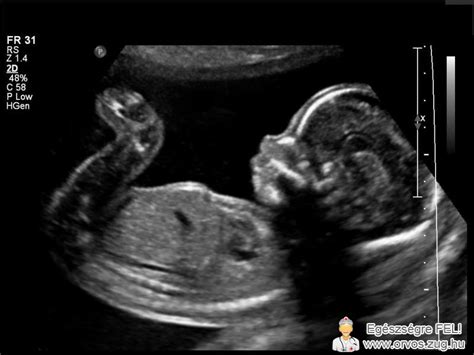

Hüvelyi ultrahangvizsgálat: Az endometriumpolipok kezdeti diagnózisának elsődleges eszköze a transzvaginális ultrahangvizsgálat (TVUS). Az endometrium polipjai „világosabb” elváltozásként jelennek meg, szabályos kontúrokkal. A képalkotás a menstruációs ciklus 10. napja előtt - a menzesz után - a legjobb, amikor a méhnyálkahártya a legvékonyabb, a hamis pozitív és hamis negatív eredmények minimalizálása érdekében.